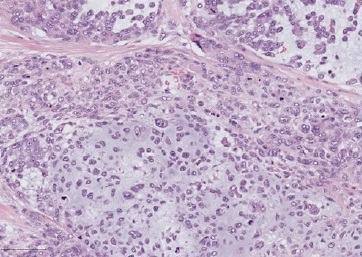

On physical evaluation, a painless 1.2-cm firm nodule was palpable sublingually, leading to the presumptive diagnosis of sialolithiasis. The mass was removed and submitted to pathological examination. Grossly, the lesion was firm and grayish with irregular borders (Figure 2). Histopathology showed a malignant lesion comprising neoplastic epithelial cells arranged in small nests with a large central area of chondroid matrix (Figure 3). The epithelial cells were large, with hyperchromatic and pleomorphic nuclei presenting a high mitotic rate (Figure 4). At the edge of the fragment, salivary parenchyma exhibiting ductal ectasia with scant inflammatory cells was identified.

Figure 3 Periphery of the sublingual lesion, showing sublingual parenchyma (left), and tumor with chondroid matrix (right), HE